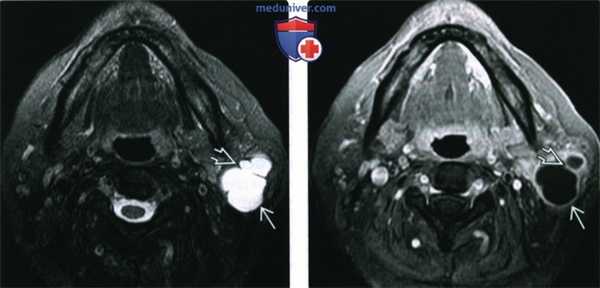

(Слева) MPT Т2ВИ FS с КУ, аксиальная проекция. Гиперинтенсивное образование поверхностной доли околоушной железы, в толще новообразования имеются перемычки. Кистозную опухоль Вартина можно спутать с обыкновенной кистой.

(Справа) МРТ Т1ВИ FS с КУ, аксиальная проекция, этот же пациент. Низкоинтенсивное образование с наличием перемычек и периферическим кольцом накопления контраста. Кольцо накопления контраста позволяет отличить опухоль Вартина от обычных кист, но, в то же время, его можно принять за признак абсцедирования. Обратите внимание на то, что исчерченность жировой клетчатки, которая говорила бы в пользу абсцесса, отсутствует.2. КТ при опухоли Вартина:

(Слева) На аксиальной МРТ (Т2 ВИ FS) в доле околоушной железы визуализируется гиперинтенсивная опухоль в с перегородками. Кистозную опухоль Уортина можно спутать с простой кистой.

(Справа) На аксиальной MPT (Т1 ВИ С+ FS) у этого же пациента визуализируется гипоинтенсивная опухоль с перегородками и контрастирующимся «ободком». Контрастирование помогает отличить опухоль Уортина от пропой костной кипы, но и позволяет прийти к ошибочному заключению о паротидном абсцессе. Обратите внимание на отсутствие уплотнения окружающей жировой клетчатки, что нетипично для абсцесса.2. КТ при опухоли Уортина: